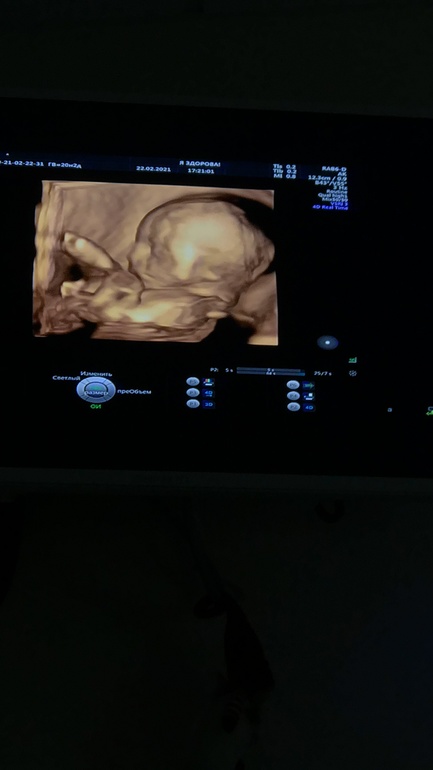

Сыночек +- на 384 грамма, идёт по сроку с небольшим опережением. В сердечке нашли хорду один в один таких же размеров и такого же расположения, как была у Аарона. Не критично, да и надеюсь что как и в случае со старшеньким, рассосётся к родам. На всех фотографиях тоже видно сходство с братом уже сейчас: выпяченная вперёд верхняя губа выдаёт))

Вот он, малышочек: